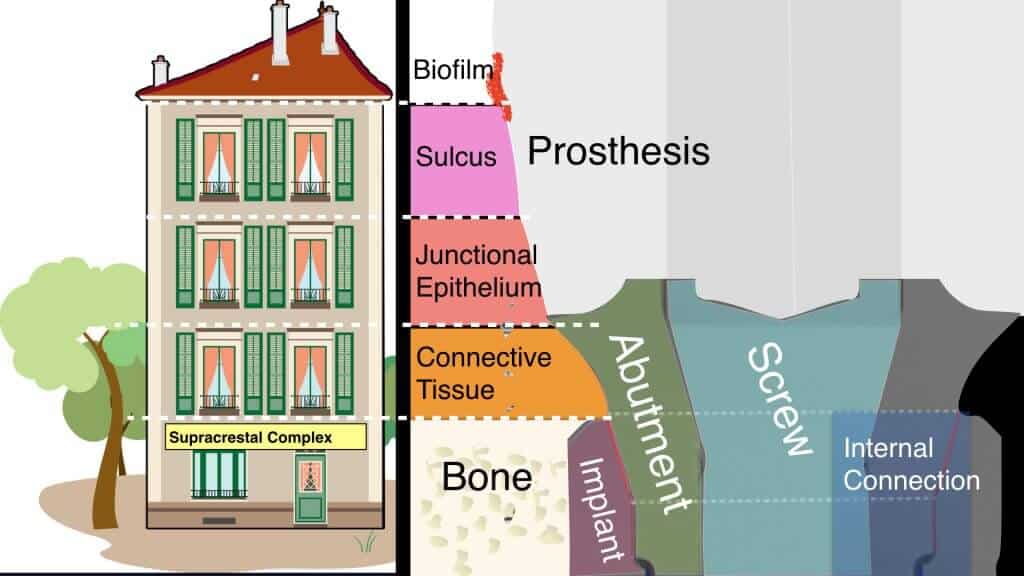

Our Cyborg is actually tiny, no more than 200 square mm. But in this tiny space, it packs 3 out of the 4 tissues of the human body, at least 3 mechanical constructions,

more than 300 types of human cells and countless numbers of bacterial species. Possible one of the most complex man-made ecosystems, the Supracrestal Complex is the tiny space defined by the cortical Marginal Bone (apicaly) and the first couple of mm of the implant prosthesis exposed in the oral environment (coronally). Rather than “supracrestal tissues” (only human tissue), or “Supracrestal Attachment” (true attachment is only the junctional epithelium), Supracrestal complex includes all 3 key players: Human Tissue, Mechanical parts and Bacteria. More than anything else, this tiny little space will be the most critical determinant of long term success or failure in Implant Dentistry.

I picture the Supracrestal Complex like a 4 storey apartment block, somewhere in the upmarket suburbs of a tropical city:

– In the Ground floor lives a married couple, Mr and Mrs Osseointegration. The husband is a rough Titanium surface, -plain or with microgrooves- and the wife is crestal bone. Their two children -the Abutment and the Screw- live well protected in their home connection.

– In the first floor lives another couple, Mr. Connective Tissue and Ms Abutmnent. They are not married, but live happily together in a partnership they call “Adhesion“. Despite pressure from their families, they do not seem inclined to formalise their long relationship.

– In the second floor, we have another married couple, Mr and Mrs Attachment. The wife is a Junctional Epithelium and the husband is a smooth surface Abutment or Prosthesis.

– In the Penthouse, lives a seasoned bachelor, Mr. Sulcus. He is a nice guy, hard working and has many friends, but he is a bit flirty and prone to adventures. The other tenants are often concerned seeing strangers coming in and out of the penthouse and are afraid that Mr Sulcus can someday get everyone in trouble.

– Finally, there is the roof. Although no humans live on the roof, it is anything but lifeless. It is exposed to daily rains and strong sunshine and frequented by pigeons, parrots, cats and others who can make a horrible mess if they are left to nest and poo unchecked.

The Supracrestal Complex includes 3 key players:

Human Tissue,

Mechanical Parts and Bacteria”